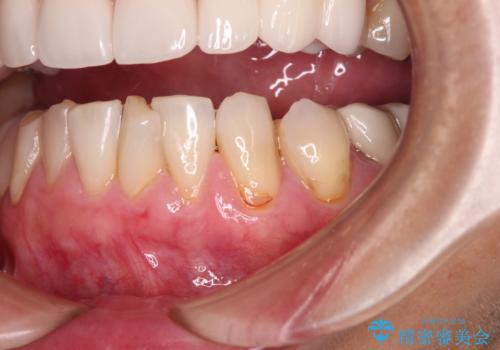

- 今まで知覚過敏の薬や歯磨き粉などを散々試しても全く改善されないとのことで来院された患者様です。

歯根面が露出しており、少し風をかけるだけでもしみてしまう状況でした。

セラミッククラウンによる治療も検討されていましたが、歯肉が非常に薄く、クラウンを装着しても将来的に歯肉退縮を起こす可能性が考えられたので、まずは歯肉移植による根面被覆を行うこととしました。